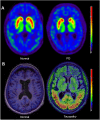

The early differential diagnosis of Parkinson disease and atypical parkinsonism is a major challenge. The use of single photon emission computed tomography (SPECT)/positron emission tomography (PET) molecular imaging to investigate parkinsonism is a fast-developing field. Imaging biomarker research may potentially lead to more accurate disease detection, enabling earlier diagnosis and treatment. This review summarizes recent SPECT/PET advances in radiopharmaceuticals and imaging technologies/analyses that improve the diagnosis of neurodegenerative parkinsonism. We are currently witnessing a turning point in the field. Integrating molecular imaging as a diagnostic technique represents an opportunity to reassess the strategies for diagnosing neurodegenerative parkinsonism. ANN NEUROL 2021;90:711-719.